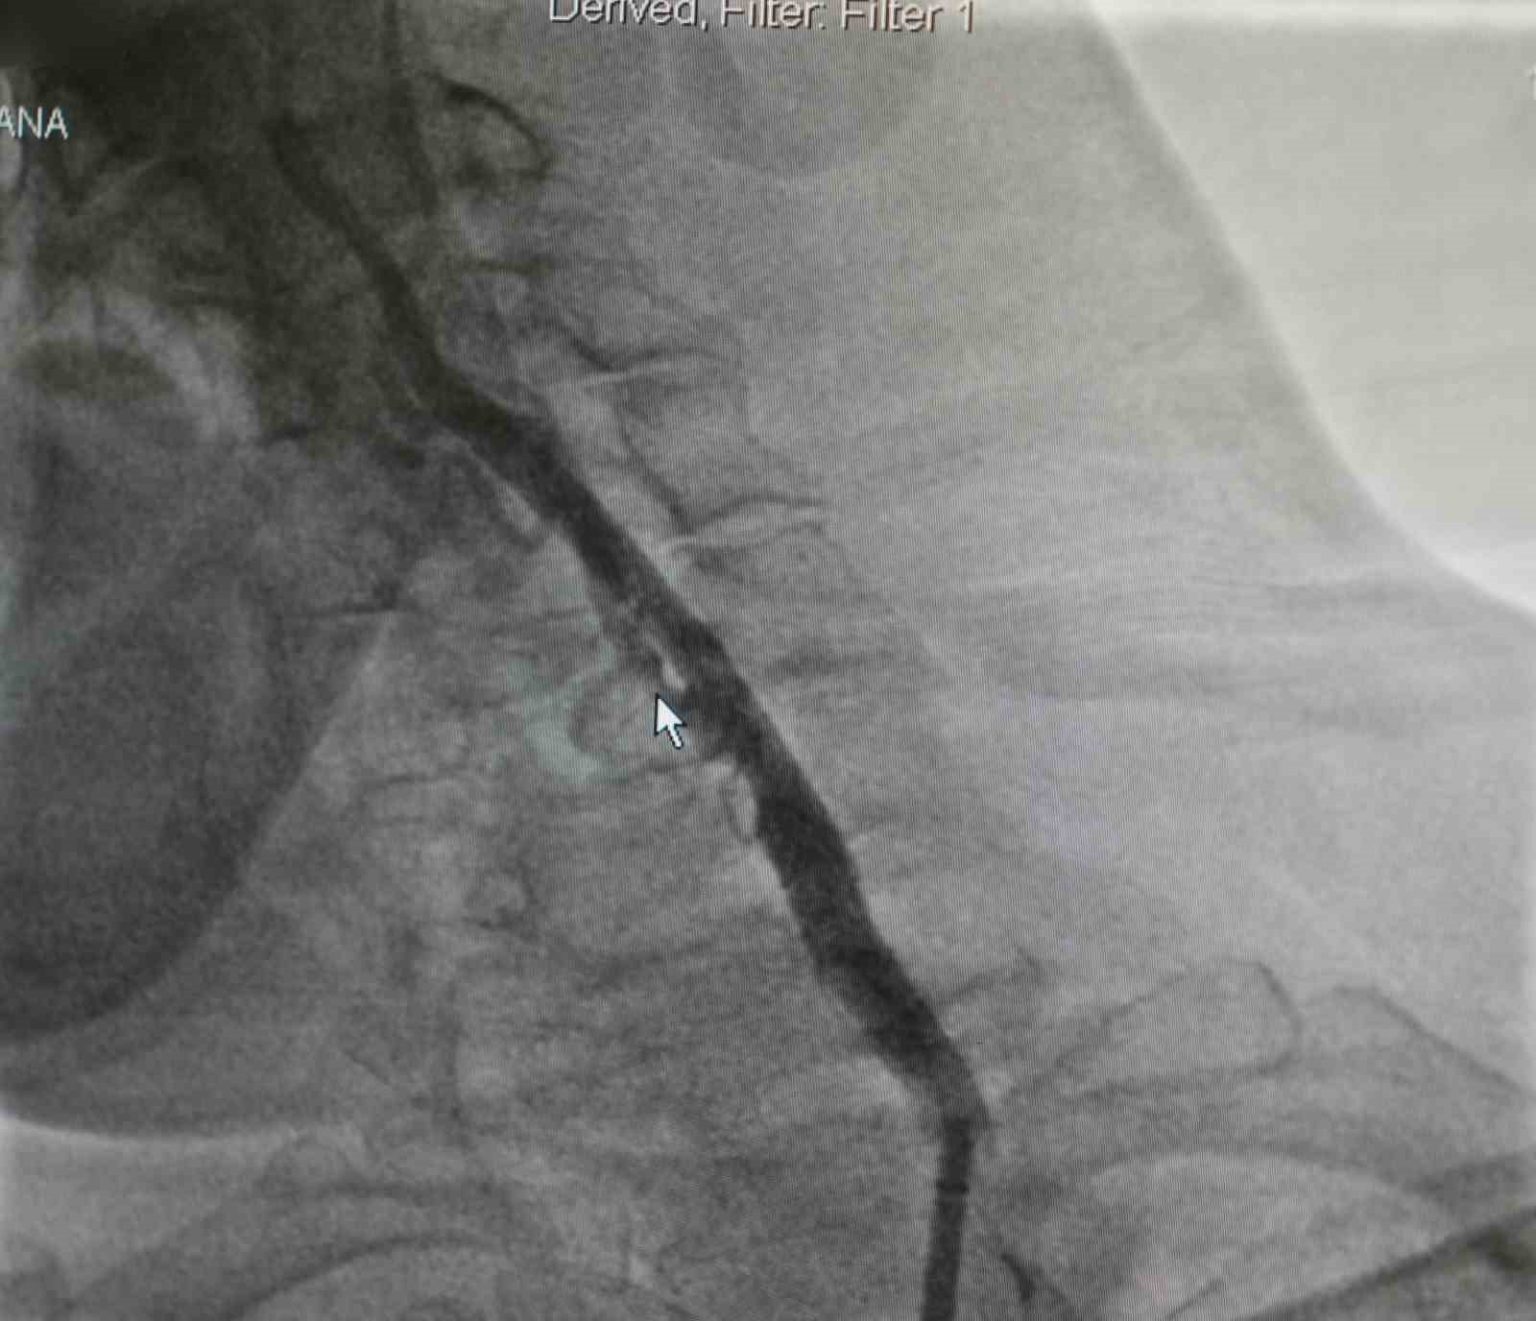

Samsun’da yaşayan Zekai Bozyel (71), 15 yıl önce bypass ve kalp kapak ameliyatı geçirdi. Rutin kontrolleri devam eden Bozyel, 20 gün önce kolunda güçsüzlük şikayetiyle nöroloji servisine yatırıldı. Yapılan tetkiklerde hastanın sağ boyun damarında yüzde 30, sol boyun damarında ise yüzde 90 oranında darlık tespit edildi. Sol taraftaki ciddi darlığın hastanın felç geçirmesine neden olduğu belirlendi. Hastanın daha önce kronik akciğer rahatsızlığı bulunması ve geçirdiği ameliyatlar nedeniyle anestezi açısından yüksek risk taşıdığı değerlendirildi. Bunun üzerine hastanın durumu kardiyoloji ekibi tarafından yeniden ele alındı. Akabinde Medicana International Samsun Hastanesi Kardiyoloji Uzmanı Dr. Öğr. Üyesi Ahmet Yanık, boyun damarında yüzde 90 darlık tespit edilen ve daha önce baypas ile kalp kapak ameliyatı geçiren hastaya ameliyatla kasıktan girerek uygulanan anjiyografik yöntemle stent yerleştirdi. Gerçekleştirilen başarılı müdahaleyle yeniden felç riskinin önüne geçildiğini belirtti.

Hastanın filmlerini inceleyip muayenesini yaptıklarını belirten Dr. Öğr. Üyesi Ahmet Yanık, “Zekai bey 15 yıl önce bypass ve kalp kapak ameliyatı olmuş, rutin takiplerinde devam eden bir hastamız. 20 gün önce nöroloji servisine yatıyor. İnme hikayesi ve kolunda güçsüzlük var. Yapılan tetkiklerinde boyun damarında darlık saptanıyor. Sağdaki boyun damarında yüzde 30, soldaki boyun damarında ise yüzde 90 civarında bir darlık var. Bu felç geçirmesine sebep olan bir darlık. Öncelikle ameliyat düşünüldü ancak kronik akciğer öyküsü ve diğer rahatsızlıkları nedeniyle anestezi açısından riskli bulundu. Biz damarın bu şekilde bırakılmasının daha riskli olacağını düşündük. Hastamızla görüşerek işlemi yapmaya karar verdik. Başarılı bir şekilde soldaki boyun damarına kasıktan girerek, herhangi bir kesi yapmadan anjiyografik olarak stent yerleştirdik. İşlem sonrası herhangi bir sorun yaşamadık ve hastamızı taburcu ettik. Müdahale edilmemesi durumunda daha ciddi bir felç riski söz konusuydu” dedi.